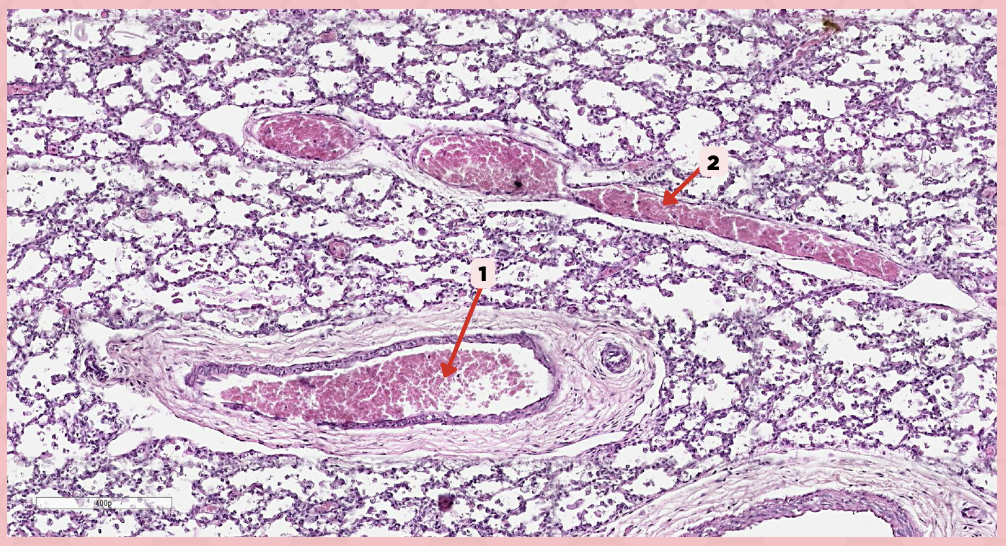

Deoxygenated blood

What type of blood does vessel No. 1 carry?

Connective tissue septae

Where would No. 2 be located?

Pulmonary artery

Identify the structure labeled as 1.

Tributary of pulmonary vein

Identify the structure labeled as 2.

Oxygenated blood

What type of blood does this vessel supply?

Bronchial artery

Identify the structure labeled as 1.